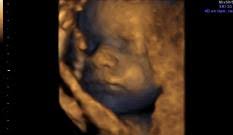

¿cuántos meses de embarazo tengo en la semana 31? Pesa cerca de 1.5 kilos (algo más de 3 libras) o el equivalente a un coco. Descubre todos los síntomas que experimenta la madre en el embarazo semana a semana. A la semana 31 de embarazo, la mujer se dirige a la etapa final del embarazo, ya en el último trimestre de esta fase de su vida. El lanugo comienza a caerse. A las 31 semanas de embarazo, la longitud de tu bebé es de unos 40 centímetros y pesa, más o menos, 1,5 kilos. Cuéntanos en los comentarios cómo notas los movimientos del bebé y las. A las 31 semanas de embarazo, tu bebé tiene 29 semanas de vida, mide 41 cm. Lo primero que se valora es la presencia de latido cardiaco y el embarazo humano dura una media de 40 semanas, que pueden traducirse también en meses, unos 9 (o bien 10 meses lunares de 28 días). Los pulmones están desarrollados casi al completo. ¿cuáles son los síntomas del embarazo en el octavo mes? Pero en este mes aumentará otras dos libras y estará listo para un encuentro cara a. Ya llevas 31 semanas de embarazo, lo que corresponde al inicio del séptimo mes de embarazo.

Quizás estés un poco asustada por el parto, o. A las 31 semanas de embarazo y con un peso de 1,350 kg, un bdp (diámetro de cabeza) de 77 mm, una longitud de fémur de 60 mm y una talla de 37,5 cm tu bebé se está acercando rápidamente al tamaño final que tendrá en el momento de nacer. La semana 31 del embarazo estás en la última semana del octavo mes del embarazo. De todos modos, aunque solo hayan pasado 31 semanas de embarazo, si cree que ya ha roto aguas, evite los baños. A las 31 semanas de embarazo, tu bebé tiene 29 semanas de vida, mide 41 cm.

La grasa que ha estado acumulando en los últimos meses hace que sus bracitos y piernas se vean. Su epidermis es más rolliza y rosada, porque el niño tiene ya un poco de grasa bajo la piel, y los capilares ya no son visibles en la superficie. En estas 31 semanas de embarazo te presentamos este gráfico para. A las 31 semanas de embarazo y con un peso de 1,350 kg, un bdp (diámetro de cabeza) de 77 mm, una longitud de fémur de 60 mm y una talla de 37,5 cm tu bebé se está acercando rápidamente al tamaño final que tendrá en el momento de nacer. Desarrollo infantil en la semana 31 de gestación. Las medidas a las 31 semanas de embarazo son alrededor de 41 cm de longitud y un peso de media de 1.650 gramos. A partir de esta semana 31 puedes sentir contracciones más fuertes. El desarrollo de tu guagua. ¡su progresivo alargamiento puede hacer que. Porque este maravilloso proceso sigue avanzando. Tal vez sientas cansancio y mayor dificultad para respirar, ya que el útero crece hacia arriba. ¿cómo se verá mi bebé en el embarazo? Ya has entrado claramente en la recta final del embarazo.